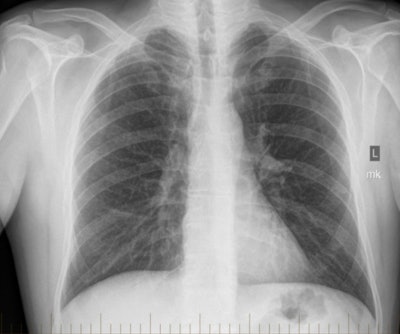

Among the 79 men, there were 56 cases of pneumoconiosis, which demonstrated as widespread opacities with bilateral upper zone predominance, according to the authors. In these cases, most of the lung was affected, with 72% of lung zones showing opacities on x-ray and 79% on high-resolution CT.

Some 71% of the miners with pneumoconiosis had ILO category 1 disease, while 21% had advanced disease. What's more, 81% of the those with pneumoconiosis had at least one feature on images that indicated exposure to respirable crystalline silica.

For other lung diseases, 18 individuals had chronic obstructive pulmonary disorder (COPD), characterized by widespread emphysema that was not dominant in any one lung zone. Five individuals had dust-related diffuse fibrosis, which presented as radiologically severe disease with irregular opacities that were dominant in lower lung zones.

The radiological findings that were of particular interest in the study were the high burden of opacities found on x-ray and CT images, as well as the presence of features associated with silica exposure in most of the individuals, according to McBean and colleagues.

What caused the high incidence of advanced disease? The authors postulated this was due to the lack of an aggressive screening program, manifested by "poor-quality chest radiographs" and a lack of image review by specialist chest radiologists who had experience with occupational lung disease. Indeed, they expressed surprise that the cases in their study were not detected earlier, given the high burden of opacities on images.